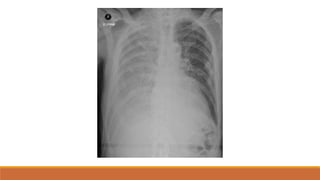

Khung xương

Bờ dưới xương sườn

Bờ dưới xương sườn vùng giữa và thấp dạng dải mờ (tránh lầm phản ứng màng xương)